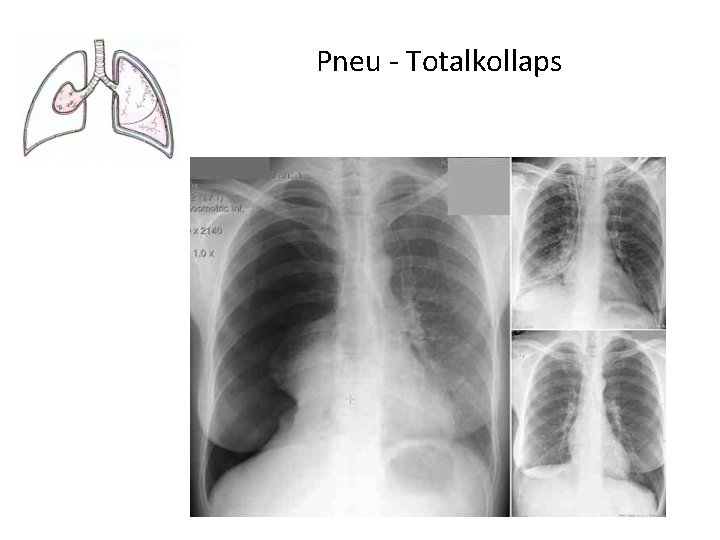

Pathologie der Pleurahöhle • Ein Pleuraerguss ist eine Flüssigkeitsansammlung im pleuralen Spaltraum • Ein Empyem ist eine Eiteransammlung im Pleuraspalt (wenn z. B. ein Lungenabszeß in den Pleuraspalt einbricht). • Pneumothorax: Wenn in den Pleuraspalt Luft tritt, hebt sich die Lunge von der Thoraxwand ab: es bildet sich der Pneuspalt eines Pneumothorax ("Pneu") aus. • Ein Hämatothorax ist eine Einblutung in den Pleuraspalt (z. B. bei Rippenfraktur). • Ein Chylothorax besteht bei Lymphe im Pleuraspalt. Die Lymphdrainage erfolgt über die viszerale Pleura. • pleuralen Tumoren • Pleuraplaques und –Verkalkungen, Pleuraasbestose

Pneu - Totalkollaps